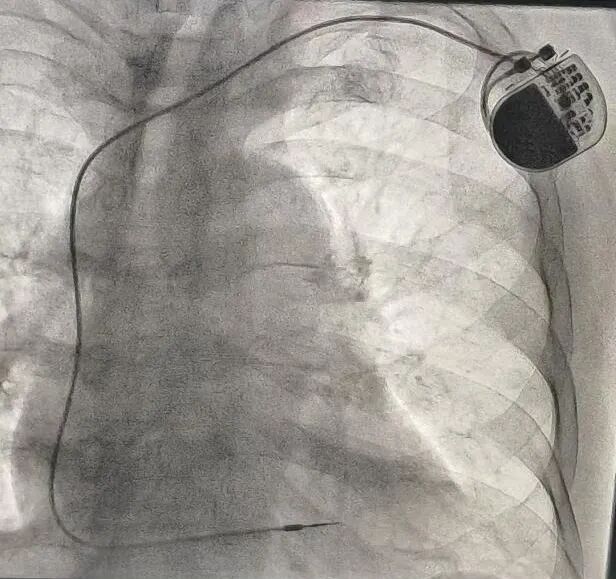

手术在局部麻醉下进行,西安交大一附院专家亲临现场指导,我院心内科团队操作。手术团队在患者左侧锁骨下区域切开一个约4cm的小口,通过穿刺血管,将电极导线精准地放入心脏右心室,另一端连接起搏器脉冲发生器,并将其埋藏于皮下囊袋中。整个手术过程顺利,历时1个多小时,术中患者生命体征平稳。术后测试显示,起搏器工作正常,参数良好。